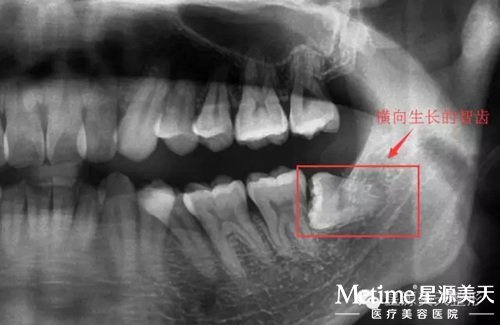

他被三博口腔的医护人员誉为全能的口腔医生,不管是拔复杂的埋伏牙/智齿、复杂的隐形矫治,还是修复类矫治,胡主任都会凭借专业的医学技能和丰富的临床经验,得以完美的解决。

每一次拔牙都需要拍片子 看牙齿的位置深度

横向生长的智齿 一般的牙医都不拔

埋伏牙、横向生长的智齿...,好多牙医都不敢拔的牙齿,对于胡主任来说,这都不算什么,20分钟就能搞定!